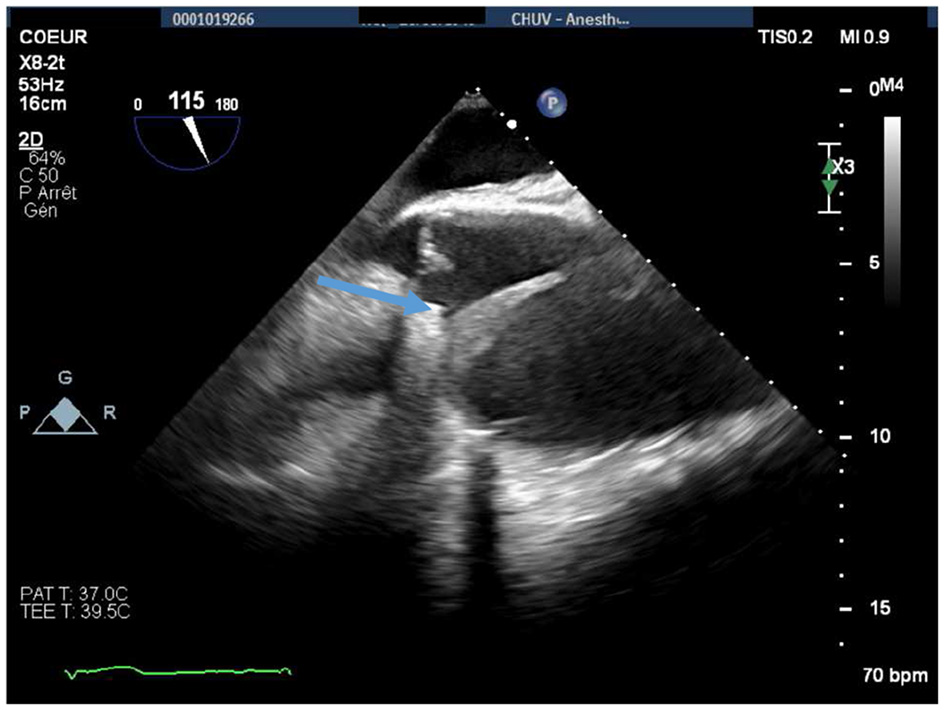

Figure 3

Perioperative midesophageal long-axis view showing a thickened (5 mm) dissection flap localized in the proximal ascending aorta, immediately after the origin of the right coronary artery (blue arrow). The maximal diameter of the ascending aorta was 74 mm.